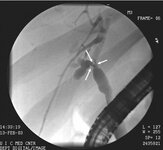

ERCP image of hilar cholangiocarcinoma: Klatskin's tumour with stricture of duct bifurcation (arrows)

From the collection of Dr Joseph Espat; used with permission